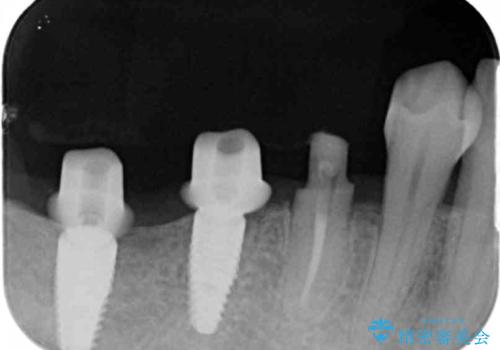

インプラント・ブリッジ補綴を含む、歯周病全顎治療

全体的な歯周病検査を行い、多数の残すことのできない抜歯の必要な歯を認めたため、残せる歯に対しての徹底的な歯周病治療、失った歯に対しブリッジ・インプラント治療を全顎的に行っていくこととしました。

長期間にわたる治療後、歯に対する意識も大きく変わりプラークコントロールも非常に良くなりました。

数ヶ月に一度のチェックをしっかりと行い、ブリッジ・インプラントが長期間使用できるようメンテンスを行っていきます。